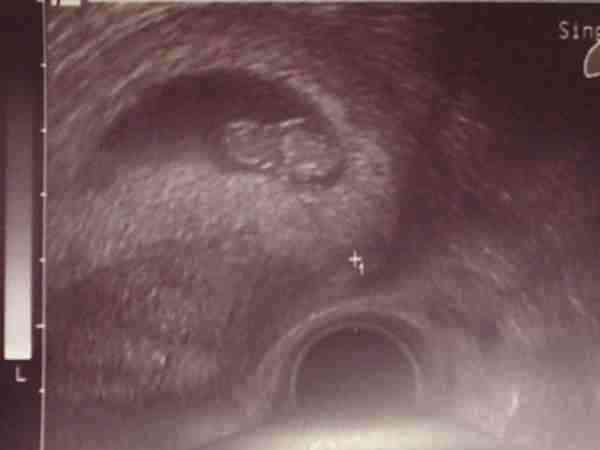

Plusz fogi felíratás, UH.